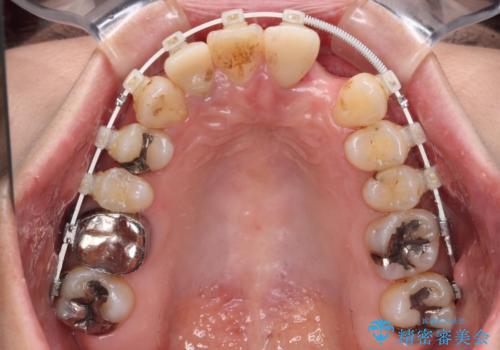

- 非対称な前歯や奥歯の目立つ銀歯を気にして来院された患者様です。

左上前から2番目の歯は、以前裏側に位置していたことから抜歯をされていましたが、前歯の非対称が長年気になっているとのことでした。

矯正治療によって前歯にスペースを作り、左右対称となるようにオールセラミッククラウンにて補綴治療を行うとしました。

他にも奥歯の咬み合わせに問題があったので、全顎的な矯正治療を行い、前歯以外にも口を開けたときに目立つ奥の銀歯をセラミッククラウンにて補綴治療を行うこととしました。